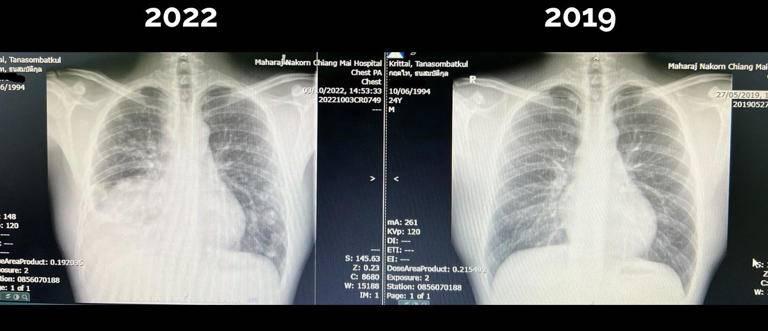

นายแพทย์ กฤตไท ธนสมบัติกุล อาจารย์แพทย์ ภาควิชาเวชศาสตร์ครอบครัว คณะแพทย์ศาสตร์ มหาวิทยาลัยเชียงใหม่ อายุ 28 ปี ได้ออกมาเปิดเผยเรื่องราวการพบว่าตนเองเป็น “มะเร็งปอดระยะสุดท้าย” ในช่วงอายุที่กำลังมีความสุข กำลังจะแต่งงาน กำลังประสบความสำเร็จในอาชีพการงาน ซึ่งโพสต์ต่าง ๆ ของเขา มีผู้แชร์ในสังคมออนไลน์เป็นจำนวนมากกว่า3แสนครั้ง

ทั้งนี้ นายแพทย์กฤตไท ระบุว่า เขา ไม่สูบบุหรี่ ทานอาหารสุขภาพ และใช้ชีวิตอย่างดีที่สุดเท่าที่คนหนึ่งจะดีได้ และแม้จะพบว่าเป็นมะเร็งปอดในระยะสุดท้าย “ผมไม่เสียดายชีวิตที่ผ่านมาเลย” เพราะ “มันคงจะดีมาก ๆ ถ้าการที่ชีวิตสั้นลงของผมสามารถเป็นกำลังใจ เป็นพลังให้กับคนที่ยังมีชีวิตอยู่ต่อ”